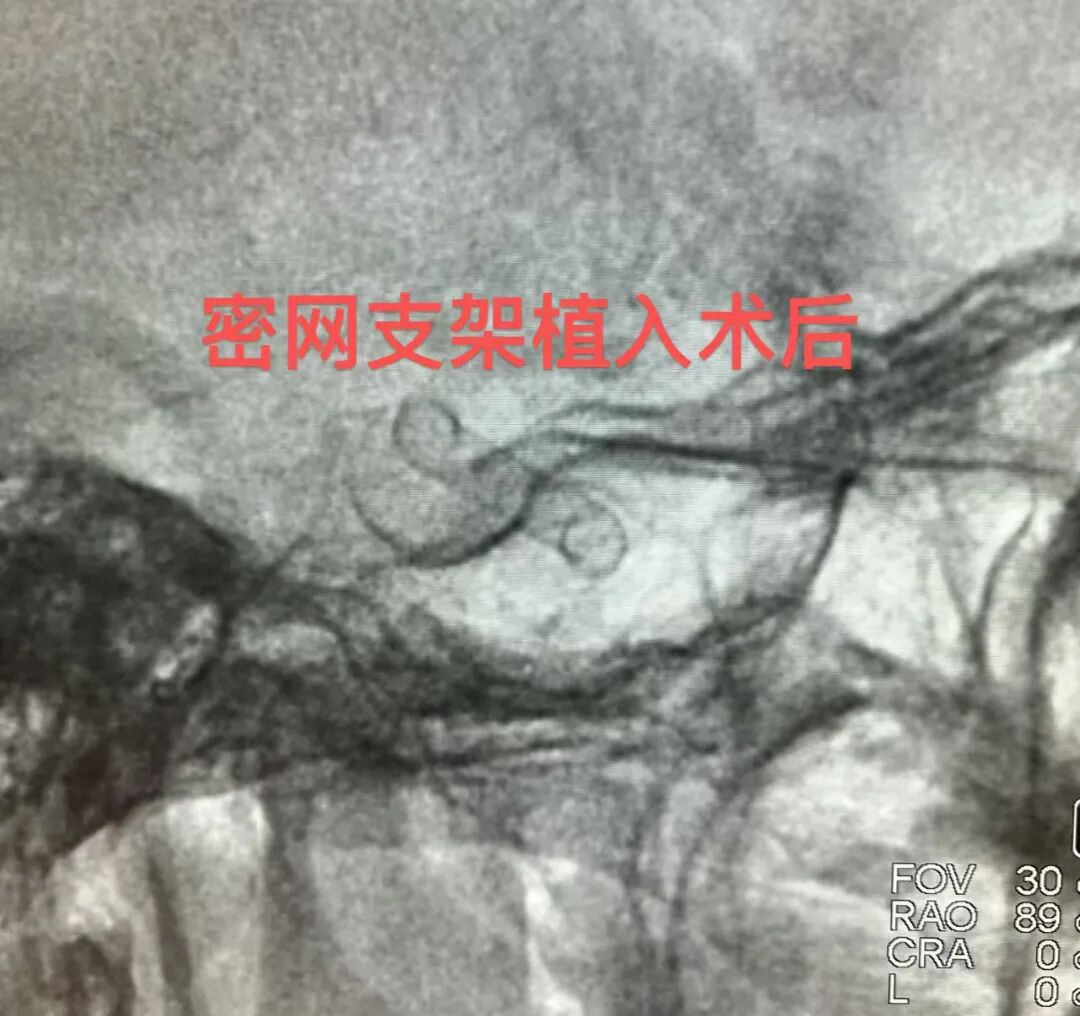

患者半年前还赫然在目的动脉瘤,

如今几乎消失不见,

只留下通畅的血管和完好的支架,

术后造影显示:支架打开贴壁良好,动脉瘤内造影剂明显滞留,载瘤动脉血流通畅。意味着神经内科介入团队成功将这颗“炸弹”拆除了。

从术前的精准规划,到术中的毫厘操作,再到术后的规范随访——每一个环节的严谨,才换来今日的“完美答卷”。这不仅仅是一个家庭重新回归安宁生活的希望,更是对神经介入团队最好的“元宵节礼物”。